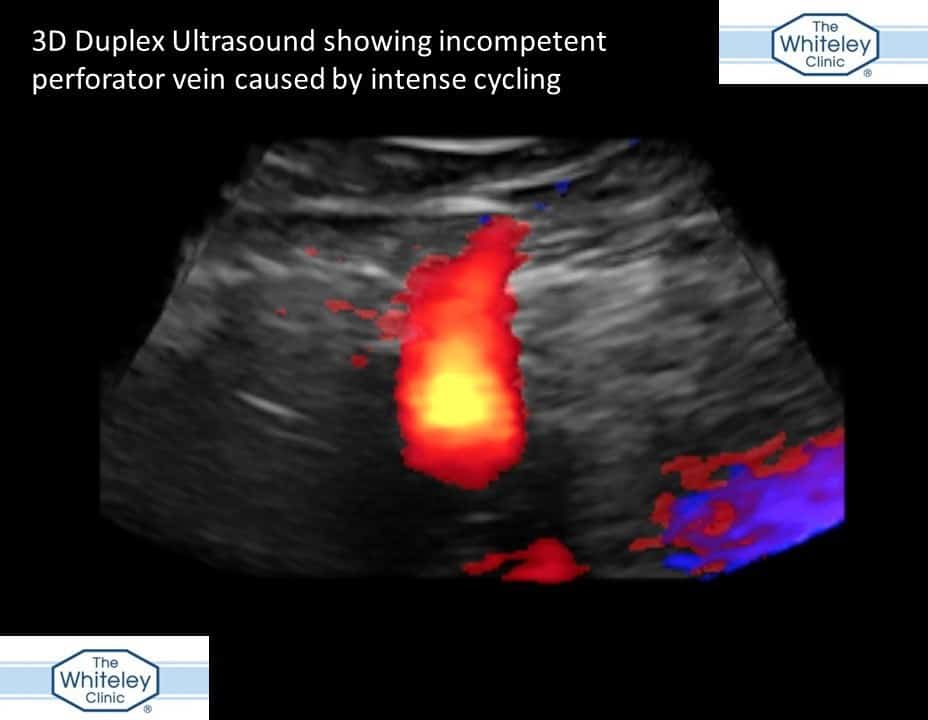

We have always suspected that some people can get varicose veins caused by cycling. Many people who cycle seemed to have varicose veins. Of course, this might be because they have low body fat. It might also be because they show their legs when cycling. However, over the years we have noticed that many patients with a certain sort of varicose vein caused by perforators, seem to be more likely to be cyclists. In addition, keen cyclists seem to get varicose veins back again more commonly than we would expect. This is almost always due to new incompetent perforators causing the varicose veins. Unfortunately, there has not been any proof showing the link between cycling and formation of varicose veins. Today The Whiteley Clinic researchers have published a case that may show the link. The case is discussed in detail in the publication that can be viewed online through this link: Link to case report The lady in question appears to have developed her varicose veins suddenly during intense cycling. This was proven by three-dimensional ultrasound scanning, performed by the expert vascular technologists at The Whiteley Clinic.

Varicose veins caused by intense cycling - perforator incompetence 3D duplex - The Whiteley Clinic Nov 2017